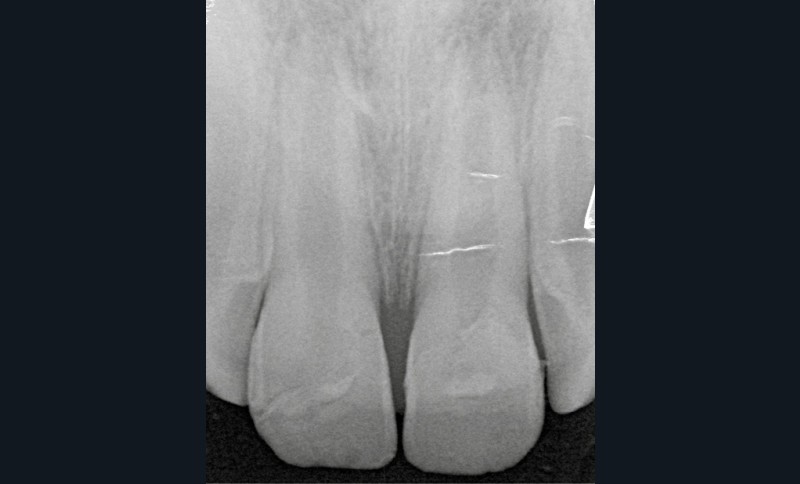

- une fracture corono-radiculaire avec effraction pulpaire de 11 et 21 (fig. 1 et 2) ;

L’examen radiologique montre que les racines de 11 et 21 ne sont pas totalement édifiées (fig. 3). La priorité sera alors de conserver la vitalité pulpaire de ces dents immatures.

À une semaine, la radiographie (fig. 8) permet d’observer le positionnement des fragments. Les tests de sensibilité se révèlent positifs pour 11 et 21.